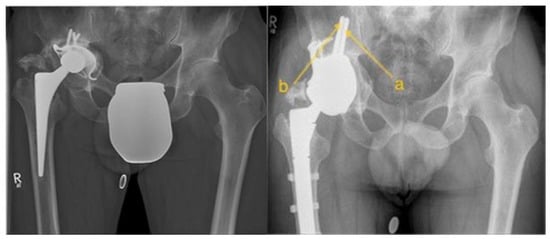

Figure 1. Illustration of the preoperative condition on the left side and the postoperative outcome after PPR with transiliac fixation on the right side. (a) TIFp, (b) TIFs.

All consecutively planned individual pelvic replacements between 2014 and 2024 in a reference center for revision surgery were retrospectively analyzed. In all successfully implanted PPRs, the digital planning was analyzed to determine the optimal TIF. All planning was carried out in close collaboration with the prosthesis manufacturer’s engineers from Implantcast GmbH, Buxtehude Germany and approved by MW, and from 2020, always by two of the surgeons involved. The successful implantation was performed by surgeons MW, CG, and YH (see Figure 1).